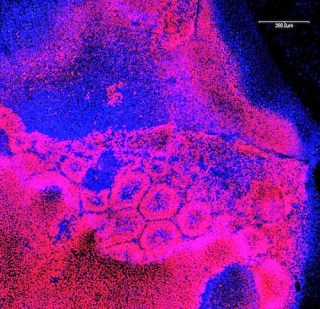

| In the first clinical trial using iPS type stem cells the stem cells will be matured into retinal cells like these. |

Interview about first iPS stem cell trial. Japan’s Riken Institute has already begun recruiting patients with blinding macular degeneration for the first ever trial in which the patients would receive cells matured from embryonic-like iPS cells made from their own tissue. With the possibility that the immune system would not reject these cells since their genetics so closely match the patient’s, a great deal of hope and anxiety in the field rests on this trial. While stem cells have been made from the tissue of the first set of patients, no transplants will happen until the cells have been tested for safety for a year. In this interview in Slate, the lead researcher Masayo Takahashi explains why she thinks the cells will be safe.